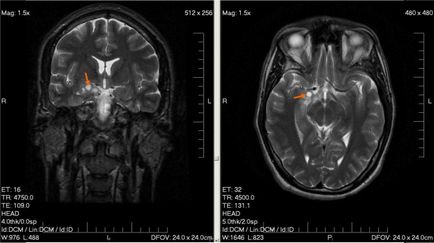

O metodă mai informativă de examinare este MRT creierului. Această metodă de scanare nu este periculoasă pentru corpul bebelușului și face posibilă detectarea chiar a tumorilor de mici dimensiuni, toate formațiunile patologice.

O altă metodă de diagnostic este tomografia computerizată.